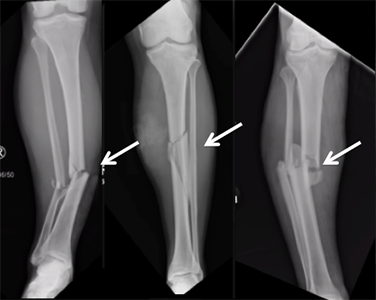

A fractured tibia, like the one sustained by Aidan Hutchinson, is a serious injury commonly caused by high-impact collisions, which are frequent in contact Sports such as football. The tibia, or shinbone, is the stronger and larger of the two bones in the lower leg, responsible for bearing much of the body’s weight, making these fractures both painful and debilitating. In Hutchinson’s case, the injury occurred during a sack, where significant force was exerted on his leg. Tibia fractures can vary widely in severity, ranging from minor cracks to severe breaks where the bone shatters or dislocates.

Hutchinson’s injury required immediate surgery, a typical approach for treating more severe fractures, especially if the bone is displaced or if there’s considerable damage to the surrounding muscles and tissues. This procedure often involves inserting metal rods, plates, or screws to realign and stabilize the bone, allowing for proper healing. After surgery, he will likely need a period of immobilization, where the leg is kept in place to facilitate bone regrowth and prevent further injury.